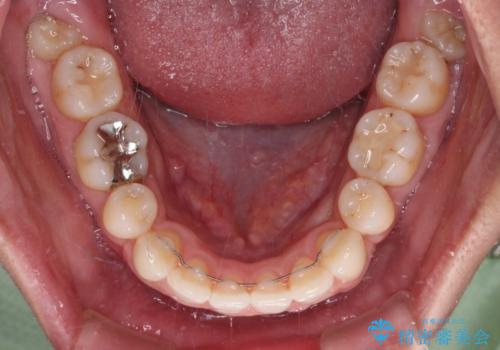

- くちばしのような前歯の突出感を気にして来院された患者様です。

上下左右第一小臼歯4本を抜歯して、積極的に口元を引っ込めるよう、ワイヤー装置にて矯正治療を行うこととしました。

抜歯矯正を行ったことで、顎先のつっぱり感や口元の閉じにくさを解消することができました。